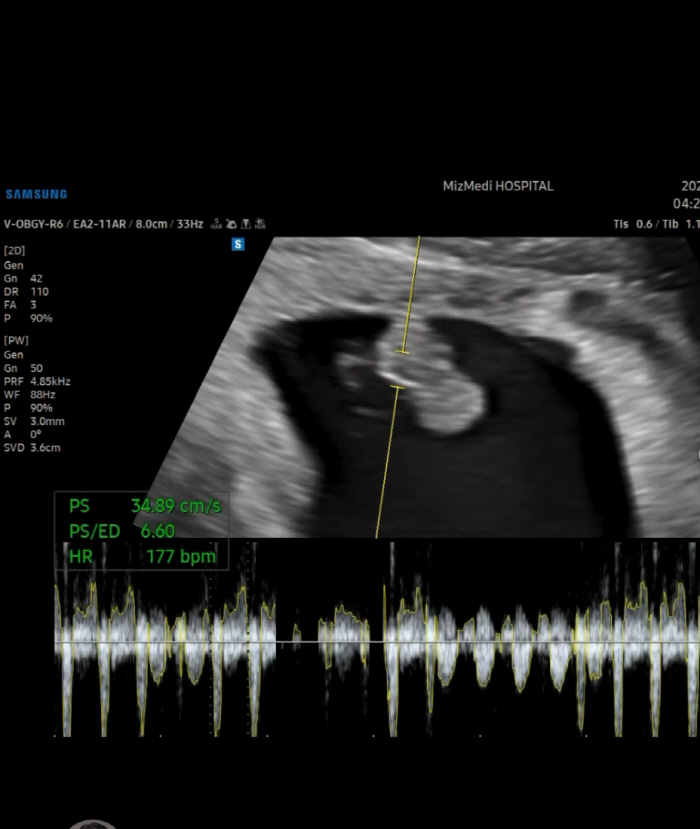

그러면서 "하여튼 저보다 제 팔로워 분들이 궁금해하실 것 같아서 심장소리 가져왔어요!"라며 초음파 영상을 공개했다.